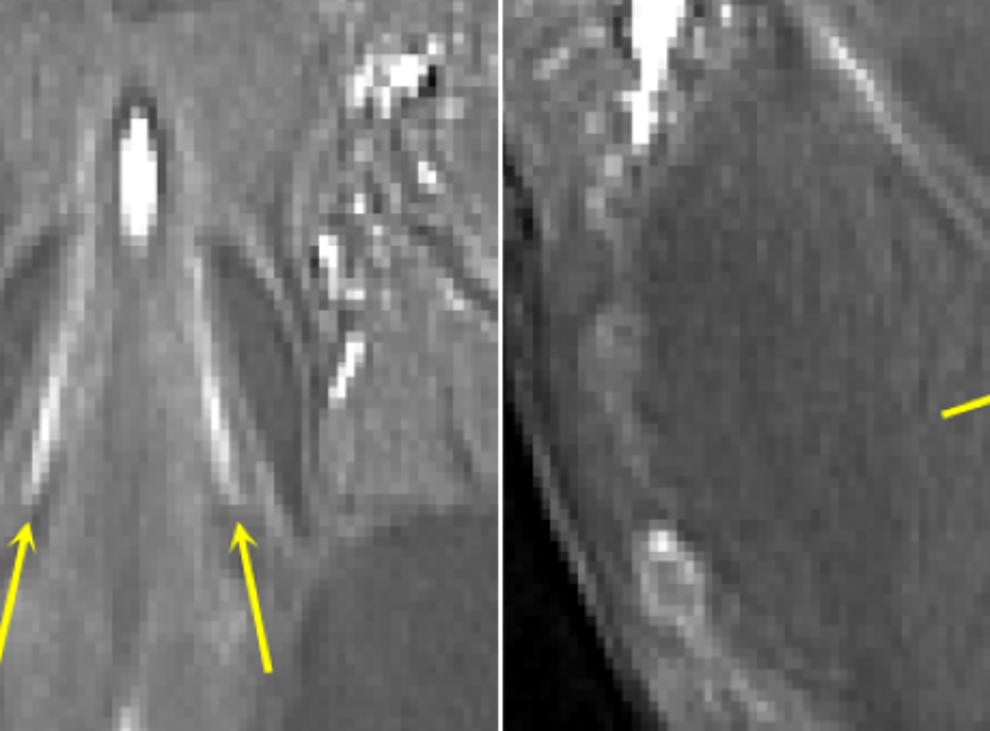

Për të kuptuar shkaqet e këtyre simptomave njohëse, studiuesit në Universitetin e Kembrixhit përdorën një skaner të ri MRI me fuqi ultra të lartë “7T” në Qendrën e Imazhit të Trurit Wolfson.

7T i referohet fuqisë së fushës magnetike – shumica e skanerëve MRI priren të jenë 3T ose më poshtë.

Skanerët 7T, të cilët kanë fusha magnetike ultra të forta, mund të ofrojnë rezolucion të lartë dhe tregojnë detajet më të vogla të trurit.

“Nga ky skaner kanë më shumë gjasa të përfitojnë ata me dëmtim të locus coeruleus – dhe sa më i madh të jetë dëmi, aq më shumë përfitim do të kenë. Skaneri ultra i fuqishëm 7T mund të na ndihmojë të identifikojmë ata pacientë që mendojmë se do të përfitojnë më shumë”,ka deklaruar Ye.